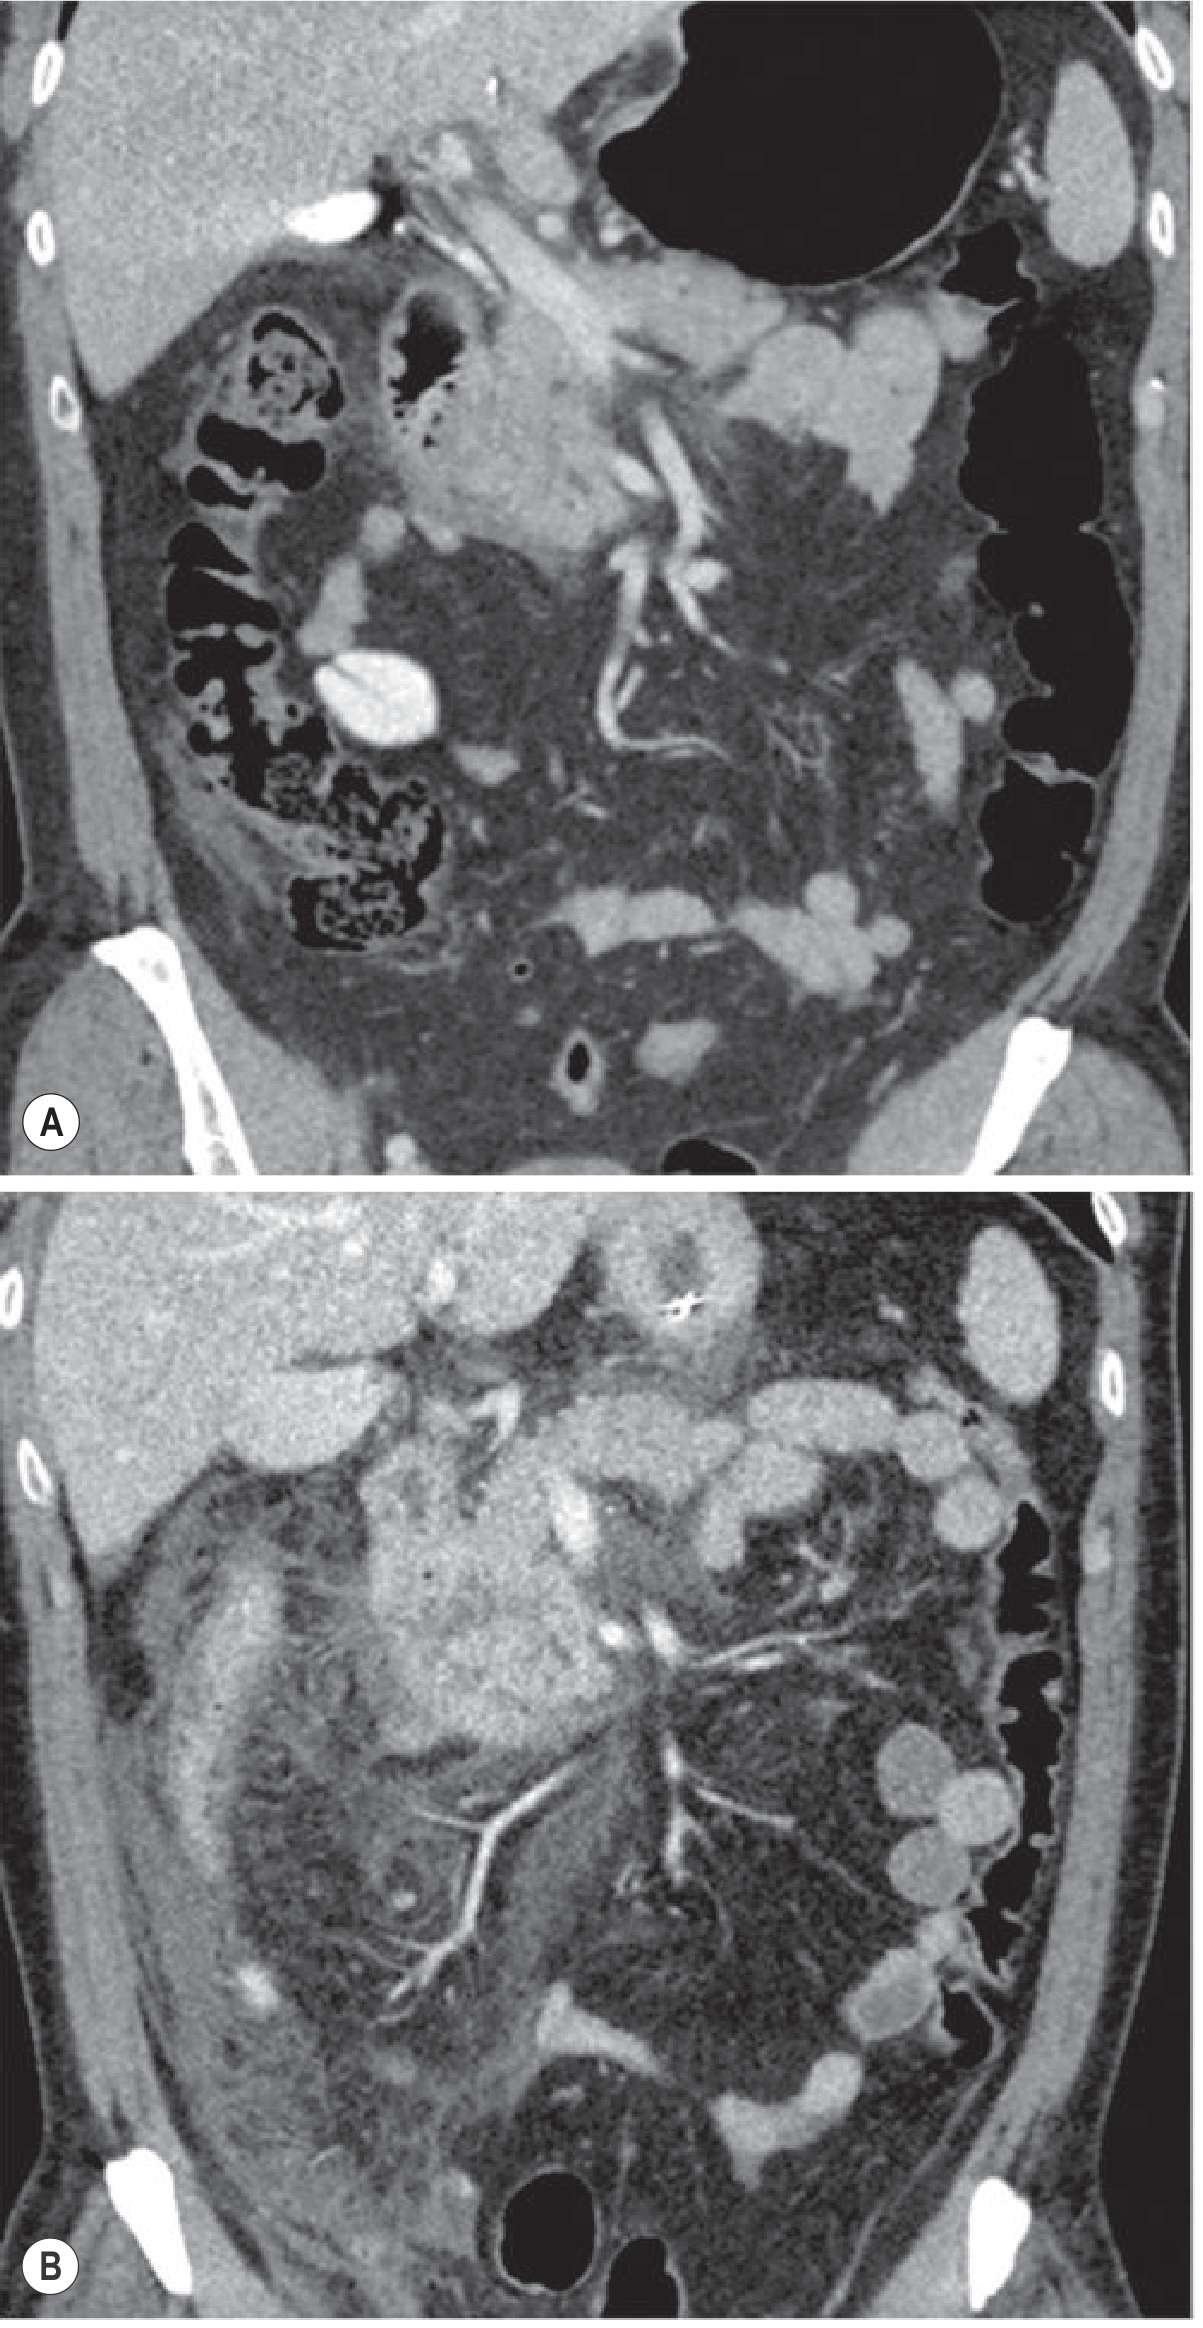

CT Timing in Acute Pancreatitis — Panel A (12 hours) shows minimal signs; Panel B (day 3) reveals much more severe inflammation and necrosis

Fig. Appropriate timing of CT in acute pancreatitis: (A) CT at 12 hours shows only minimal signs; (B) follow-up CT on day 3 demonstrates much more severe inflammation. — Grainger & Allison's Diagnostic Radiology